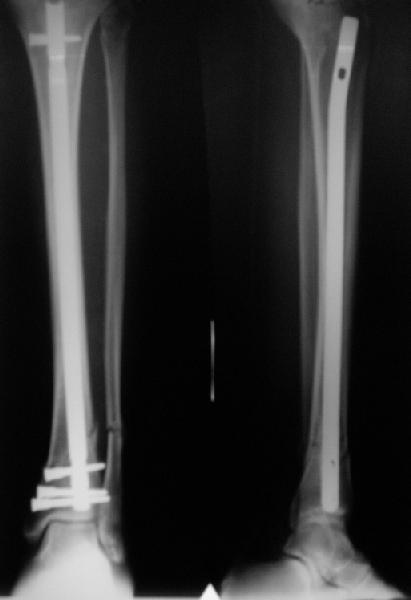

In delayed cases acute length restoration performed only in the tibia may leave the fibula shortened thus change the mortise. So it is reasonable to restore length of both bones simultaneously by distractor and fix the fibula not with open reduction and plating but just by a single perQ screw. Example attached.